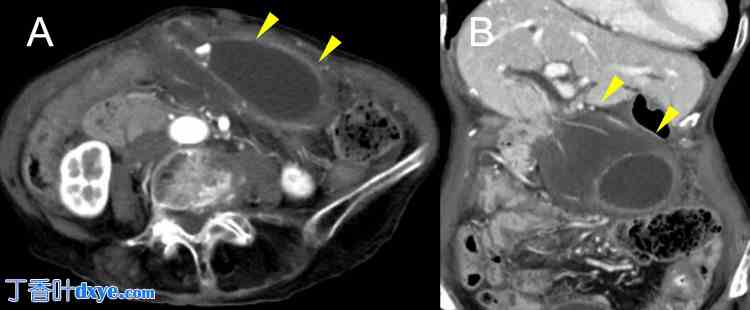

CT 影像显示胆囊壁明显增厚,并伴有水肿性改变。磁共振胆胰管造影 (MRCP) 显示胆囊颈部有扭转样缺损(图 3)。

图 3. 病例 2 胆囊扭转的放射学表现。

(A) CT 图像显示胆囊壁明显增厚和水肿。

(B) MRCP 图像显示胆囊颈部有扭转样缺损。